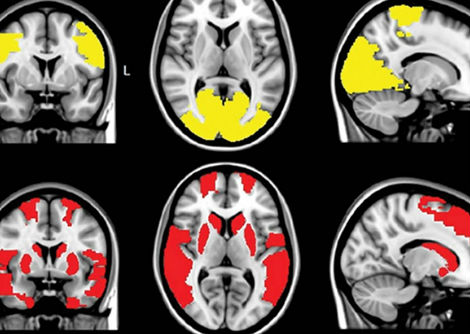

في تحليلهم ، قام الباحثون وراء الدراسة الجديدة بتقييم مجموعتين من الأشخاص على مدى ست ساعات ونصف: قامت مجموعة واحدة من 24 شخصًا بأداء مهام معرفية صعبة تتغير كثيرًا ، بينما قامت المجموعة الأخرى المكونة من 16 شخصًا بأداء مهام سهلة نادراً ما تتغير. في عدة نقاط خلال التدريبات المعرفية ، أجرى الباحثون مسحًا ضوئيًا لقشرة الفص الجبهي الأيسر الجانبي للمشاركين باستخدام التحليل الطيفي بالرنين المغناطيسي ، والذي يكتشف التغيرات الكيميائية الحيوية في الدماغ ويستخدم بشكل شائع لتشخيص الأورام. كشفت عمليات المسح أن مجموعة المهام الصعبة لديها مستويات أعلى من الناقل العصبي الغلوتامات في تلك المنطقة من الدماغ في نهاية اليوم مقارنة بمجموعة المهام السهلة.

أوضحت هذه النتيجة للباحثين أن الإرهاق العقلي يمكن أن يكون نتيجة لانتشار الجلوتامات من الخلايا العصبية وبناء هذه المنطقة من الدماغ ، وربما يتسبب في عملها بكفاءة أقل. "الشيء الأكثر إثارة للدهشة بالنسبة لنا هو أننا نرى تركيز الغلوتامات انخفاض في المجموعة السهلة "، كما يقول ويهلر ، مشيرًا إلى أن الدماغ قد يقوم بإزالة الجزيء بعيدًا لإنعاش العقل عندما يكون أقل ضرائب ، كما لو كان الناقل العصبي يعمل كمنتج نفايات.